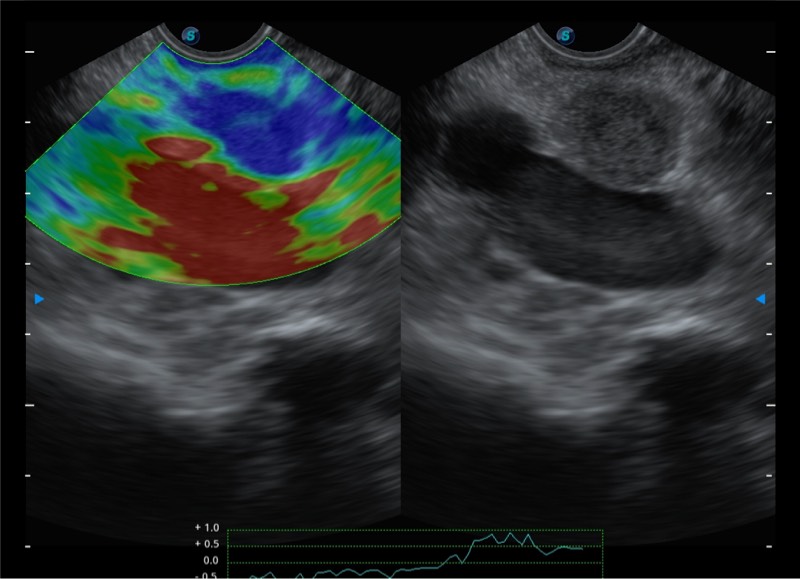

基于二十年的超声技术积累,诸侯快讯官网提供了最新一代的独立超声主机,在提供高质量图像的同时满足多学科使用。具备常见多普勒技术并提供弹性成像、声学造影等高端影像技术。新一代传感器具有更强的抗干扰能力并减少图像伪影。

4-12MHZ宽频输出